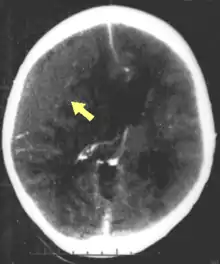

CT scan showing epidural hematoma (arrow)

Diagnosis is suspected based on lesion circumstances and clinical evidence, most prominently a neurological examination, for example checking whether the pupils constrict normally in response to light and assigning a Glasgow Coma Score.[23] Neuroimaging helps in determining the diagnosis and prognosis and in deciding what treatments to give.[75] DSM-5 can be utilized to diagnose TBI and its psychiatric sequelae.[76][77][78]

The preferred radiologic test in the emergency setting is computed tomography (CT): it is quick, accurate, and widely available.[79] Follow-up CT scans may be performed later to determine whether the injury has progressed.[10]

Magnetic resonance imaging (MRI) can show more detail than CT, and can add information about expected outcome in the long term.[23] It is more useful than CT for detecting injury characteristics such as diffuse axonal injury in the longer term.[10] However, MRI is not used in the emergency setting for reasons including its relative inefficacy in detecting bleeds and fractures, its lengthy acquisition of images, the inaccessibility of the patient in the machine, and its incompatibility with metal items used in emergency care.[23] A variant of MRI since 2012 is High definition fiber tracking (HDFT).[80]